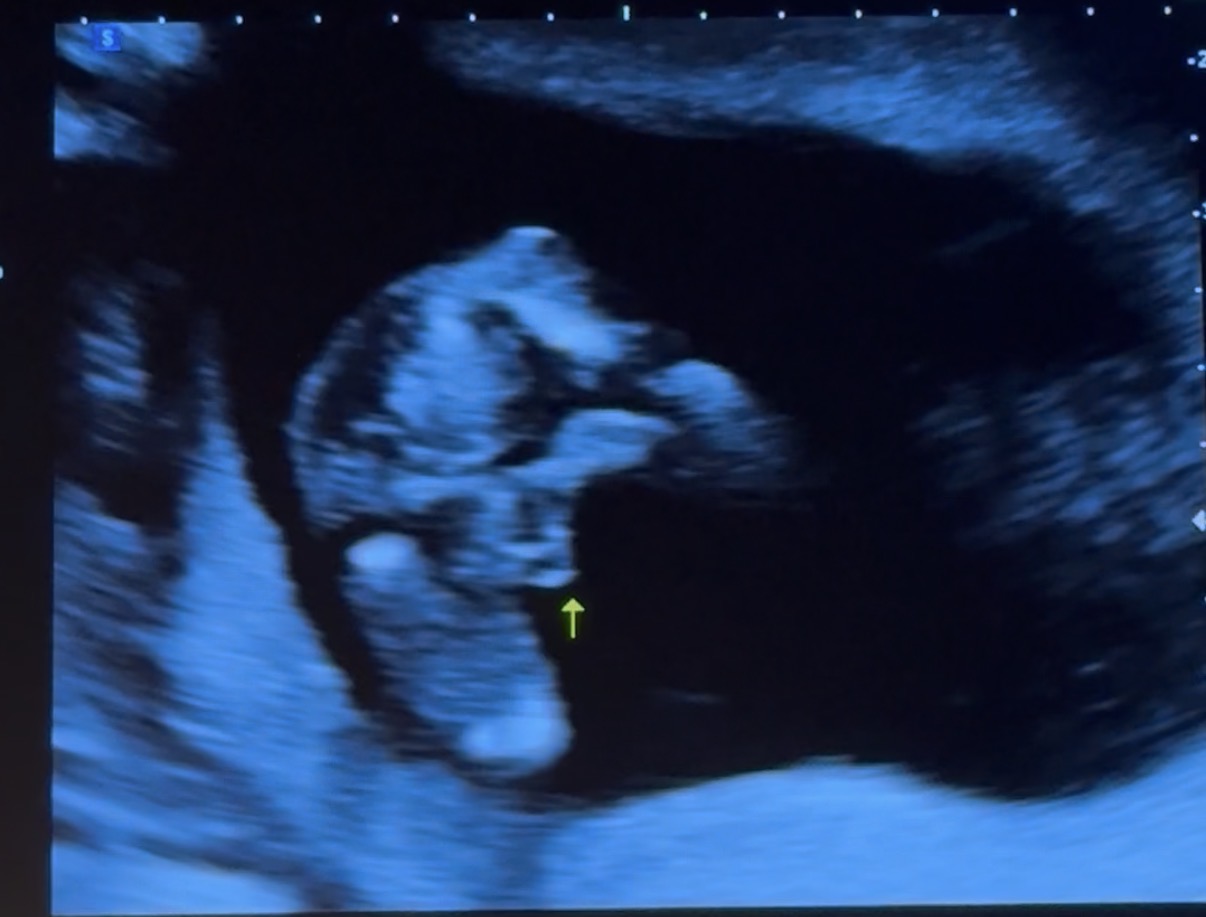

อายุครรภ์ 15 สัปดาห์ จากรูปอัลตร้าซาวด์แบบนี้ได้ลูกชายชัวร์ๆมั้ยคะ?

อัลตร้าซาวด์อายุครรภ์ 15 สัปดาห์ 5 วัน คุณหมอบอกว่าเหมือนจะได้ลูกชายแต่ยังไม่คอนเฟิร์ม ถ้าจากรูปที่ซาวด์จะได้ลูกชายจริงๆมั้ยคะ😂 พอดีเคยท้องแต่ลูกสาวค่ะ